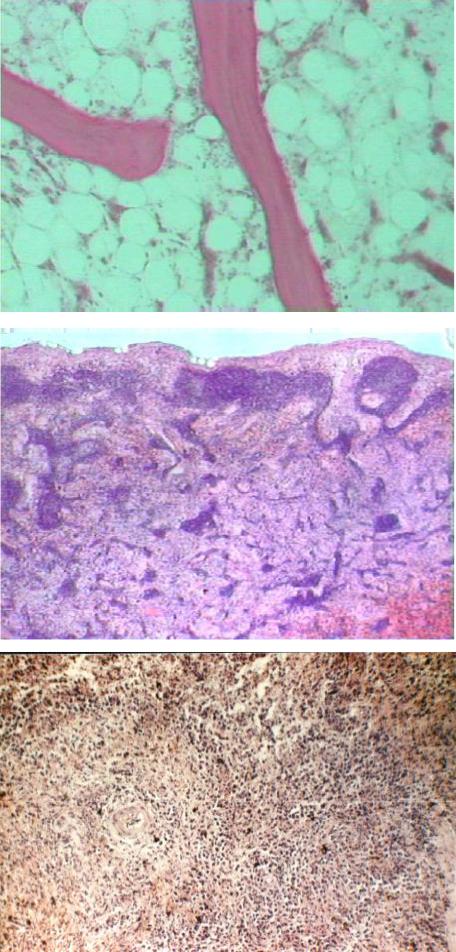

Преимущественное поражение кроветворной ткани объясняется высокой радиочувствительностью стволовых клеток. Под воздействием радиации про- исходит гибель пролиферирующих бластных кровяных клеток, нарушение их деления, что приводит к угнетению лимфомиелопоэза, постепенному опусто-

шению костного мозга (рис. 77, 78), редукции лимфоидной ткани лимфатических узлов (рис. 79) и селезенки (рис. 80).

Рис. 78. Микропрепа-

рат костного мозга грудины при гемато-

логической форме ОЛБ: исчезновение

из костного мозга грудины миелоидных клеток (окраска гема- токсилином и эози- ном, × 80)

Рис. 79. Микропрепа-

рат лимфатического узла при гематологи- ческой форме ОЛБ:

опустошение лимфо- идной ткани с редук-

цией лимфатических фолликулов и крово- излияния в лимфати- ческом узле (окраска гематоксилином и эо- зином, × 80)

Рис. 80. Микропре-

парат селезенки при гематологической форме ОЛБ: опусто-

шение лимфоидной ткани селезенки с ре- дукцией лимфатиче-

ских фолликулов и кровоизлияния в си- нусах (окраска гема- токсилином и эози- ном, × 80)